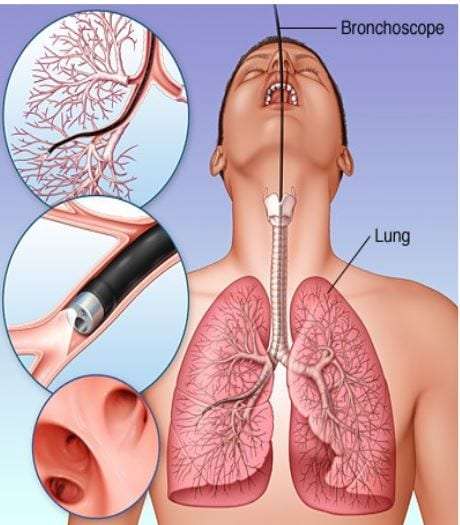

Еда для Легких и Бронхов - Полезные Рецепты